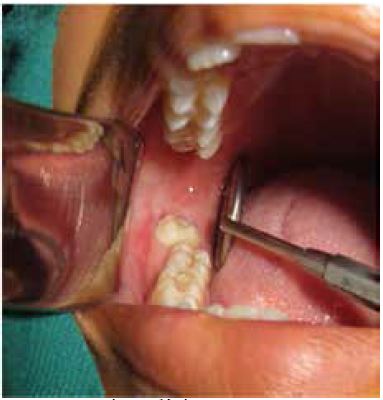

Al examen clínico se observa en el cuadrante 4, una molar retenida y vestibularizada, también se ven expuestas las caras proximales y la cara oclusal (figura 1).